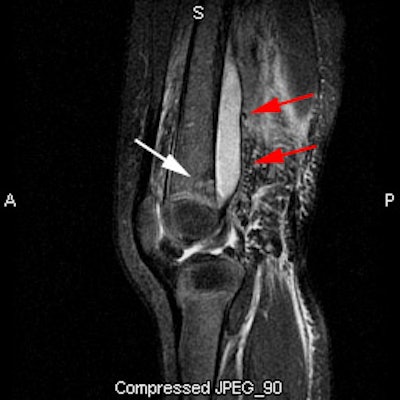

Pediatric osteomyelitis: The case below is from a 19 month old infant who presented with left leg pain. The leg was externally rotated and initially the child was thought to have a septic hip- however, a hip ultrasound was negative. A bone scan was ordered to evaluate for osteomyelitis. The flow images showed mild hyperemia in the left distal femur (click here to view flow images), but there was an elliptical area of abnormal activity on blood pool images involving the distal left femur (blue arrows). The delayed images did not reveal a significant focal finding and were interpreted as negative. The blood pool abnormality was felt to be related to a soft tissue infection. Because of a high degree of concern, an MR exam was then performed. The MR demonstrated a large subperiosteal pus collection (red arrows) and a small focus of osteomyelitis in the distal left femoral metaphysis (white arrow). This is an example of a false-negative bone scan in pediatric osteomyelitis. The late phase bone scan images may have been negative due to the small size of the focus of infection or due to imaging during the transition from "cold" to "hot" osteomyelitis. |